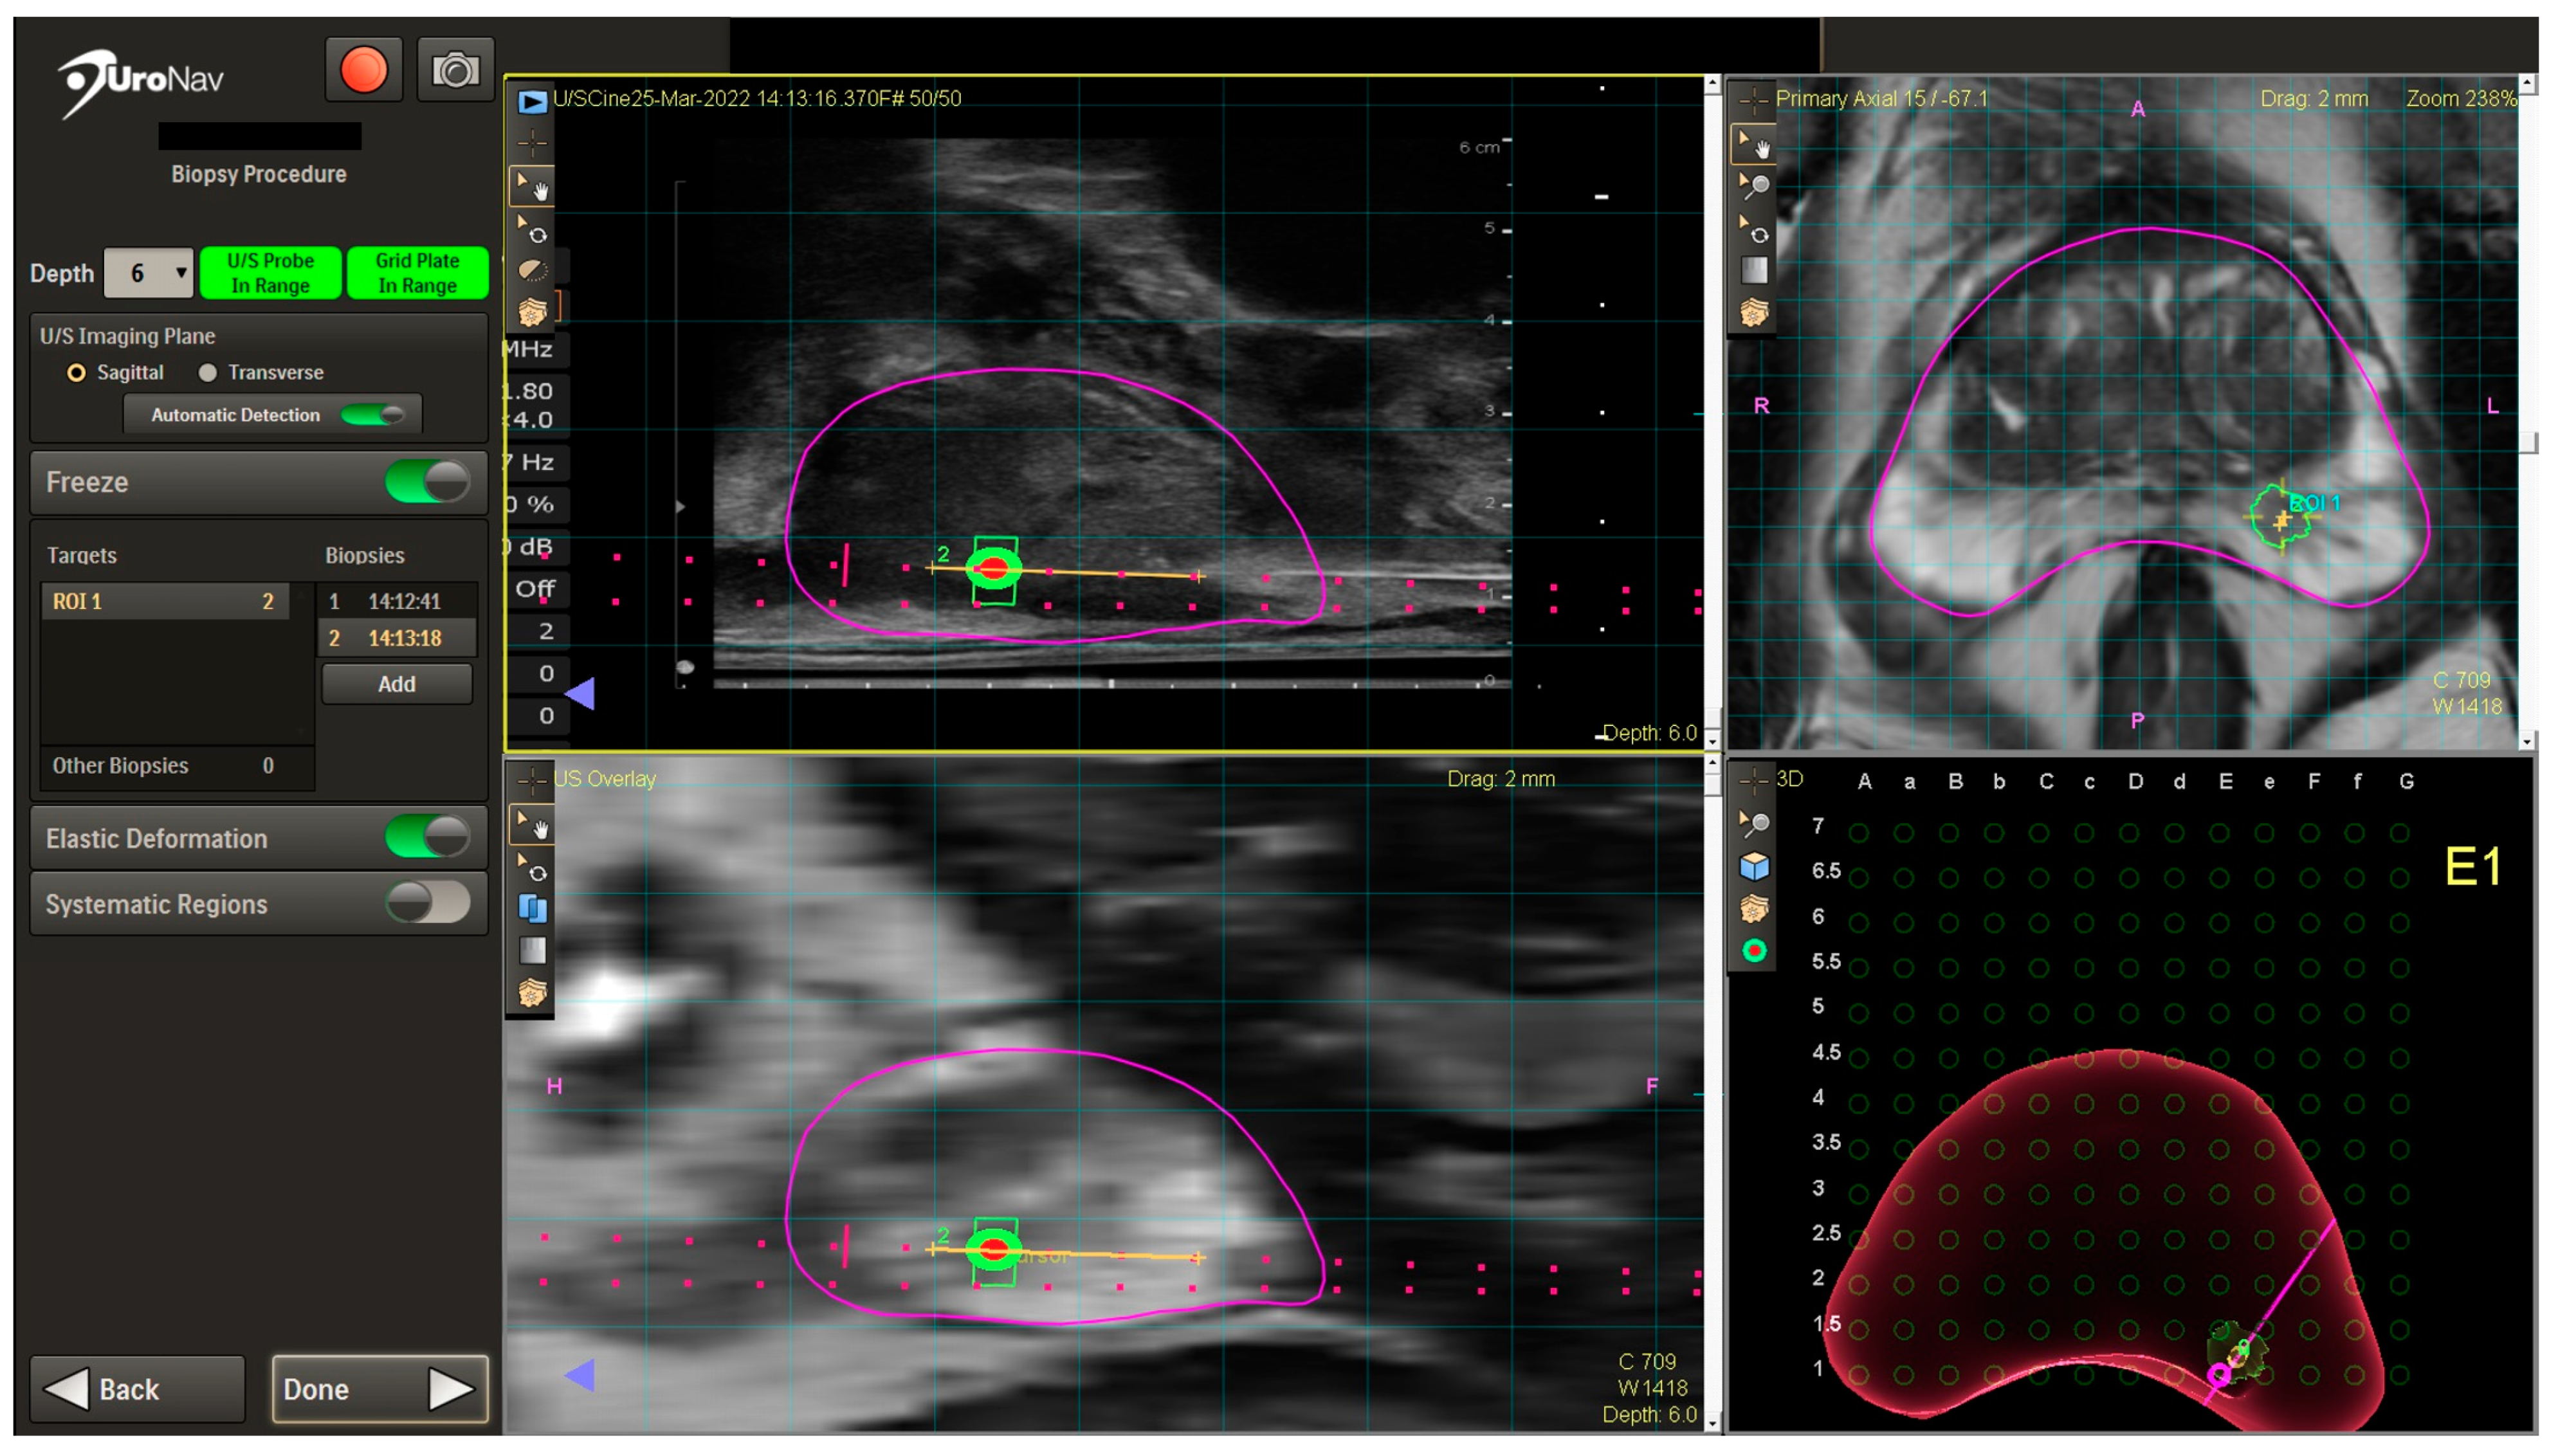

A TRUS sagittal sweep of the prostate is then performed to obtain TRUS images and dimensions, which are then fused with mpMRI images in real time on the UroNav system screen (Figure 2). After fusion, the UroNav display includes the identified ROI in the left posterior mid-gland with sagittal views (left upper and lower quadrants), axial view (right upper quadrant), and 3D rendered image with grid overlay for targeting (right lower quadrant). Biopsies are then obtained using grid holes corresponding to the location of the ROI. Cores are then taken from the ROI (four cores in this case). A systematic biopsy is then generally performed in biopsy-naïve patients. The UroNav system stores the biopsy needle trajectory for potential future use should the patient need another biopsy. At the conclusion of the procedure, the US probe is removed, perineum cleaned, and bacitracin applied. No post-procedure antibiotics or pain medications are prescribed at our institution.

Figure 2.

UroNav TP biopsy display images with ROI highlighted. The magenta outline defines the prostate. The orange line shows the biopsy trajectory. The green trapezoid is the radiologist-defined region of interest, whereas the green circle with orange center is the ideal “target”.